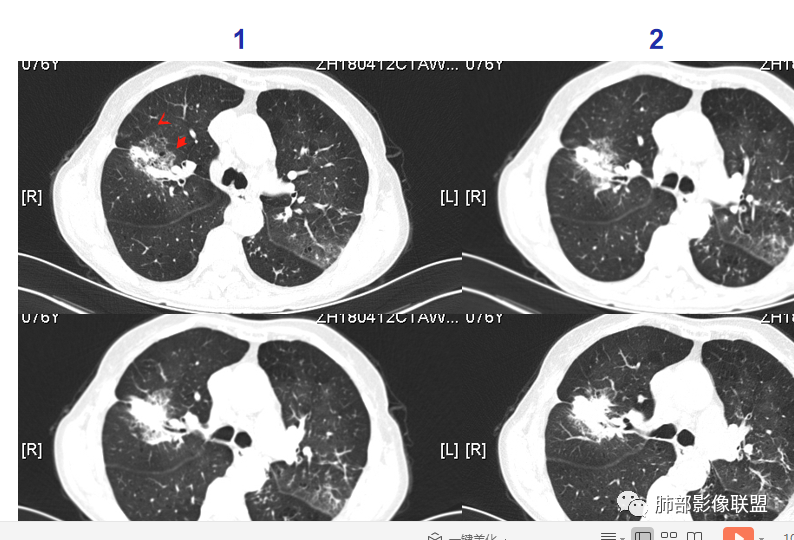

红星:    女性68岁,右肺上叶前段结节,将近7年的时间明显长大,表现出分叶毛刺及支气管截断伴胸膜凹陷,增强明显的不均匀强化,纵隔内多发的淋巴结肿大。左肺多发的斑点及条索状间质改变。考虑右肺上叶前段恶性病变,腺癌的可能性大。鉴别诊断结核或炎性肉芽肿。

宇宙:  右肺上叶不规则肿块,较8年前结节明显增大,可见分叶,毛刺,胸膜牵拉,边缘清晰磨玻璃影,上叶后段支气管堵塞,不均匀延迟强化,有坏死,纵隔淋巴结增大,考虑恶性,腺癌,鉴别炎性肉芽肿

Yishion:   时间跨度虽然大,但原病灶增大,常规需要考虑恶性肿瘤,支气管截断,不符合淋巴瘤,时间太长,说明病灶相对生长过慢,如果是鳞癌,一般破坏力很强,8年时间很难支撑得下来,常规考虑腺癌

1、老年女性,肺气肿背景,咯血多年,肿瘤标志物升高。    2、右肺上叶不规则结节影,八年后进行性增大为肿块,边缘深分叶、毛刺、棘状突起、胸膜牵拉,相应支气管壁增厚阻塞;周围局部见边界清楚的磨玻璃影;近胸壁侧见凹陷,整体呈外朝内生长。增强扫描呈不均匀明显强化,其内见坏死区,边界欠清。    3、右侧胸腔积液。纵隔见增大淋巴结。

影像及临床符合肺腺癌的诊断。8年的时间为我们展示这样一个生长过程,还是具有一定程度参考意义的。